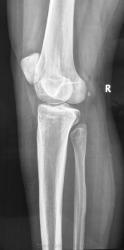

Девочка 17 лет. Беспокоят боли в в/3 голени несколько месяцев, преимущественно днём, Ночных болей нет. Клинически - некоторая болезненность при пальпации в/з правой голени по латеральной стороне. Консультировалась в частном порядке в одном из институтов радиологии. Рентгенолог по данным снимкам поставил диагноз - саркома (!) малоберцовой кости. Направлена для лечения к нам в больницу. Представлены рентгенограммы с динамикой процесса 1 месяц.

Мы убедительных данных за злокачественное образование не видим. Хотелось бы узнать мнение уважаемых коллег.

Я думаю, здесь больше данных за воспалительный процесс. У нас за последнее время тоже прошло несколько подростков с подобными изменениями, правда, в большеберцовых костях. У всех гистологически был остеомиелит.

Не вижу данных за саркому.

в целом, согласна с коллегами - не саркома, есть участок гиперостоза, в диф. ряд следует включить остеомиелит и и остеому. Но в первую очередь дообследуйте на предмет остеоид-остеомы: сделайте КТ, проведите аспириновый тест (последний, правда, работает не 100%). Возможно меня и глючит, но мое мнение, что желтой стрелкой помечено "гнездо"

На мой взгляд, вероятность остеоид-остеомы мала, все же гнездо должно быть более округлым, а здесь больше линейное просветление. У нас таких было много, сейчас вспомнила, и в малоберцовке тоже было,  пытались томографировать, когда КТ еще не было.

Ольга, я не линейное просветление имела в виду, а кнаружи от него очень мелкое уплотнение с ободком просветления по периферии. Без КТ его вряд ли удастся вывести, но теперь не узнаем...